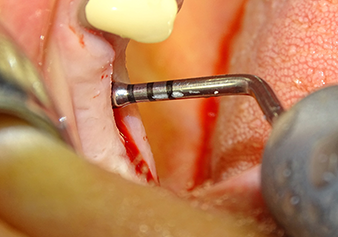

Lo strumento I2A (diametro 2,0 mm) è stato quindi impiegato per perforare il pavimento sinusale in modo graduale e su superfici molto ridotte. Tale metodo piezochirurgico previene il danneggiamento della membrana di Schneider. Durante l'utilizzo di Z25P, la membrana risultava già essere leggermente sollevata dal fluido di raffreddamento fornito attraverso la punta dello strumento (Fig. 3). La quantità di fluido di raffreddamento presente era solo del 50% per evitare che la sede dell'impianto registrasse un'elevata pressione.

La membrana di Schneider viene accuratamente scollata usando lo strumento Z25P (fase 1)

Fig.3: dopo la marcatura della posizione dell'impianto e l'espansione della sede, la membrana di Schneider viene accuratamente scollata usando lo strumento Z25P (fase 1).